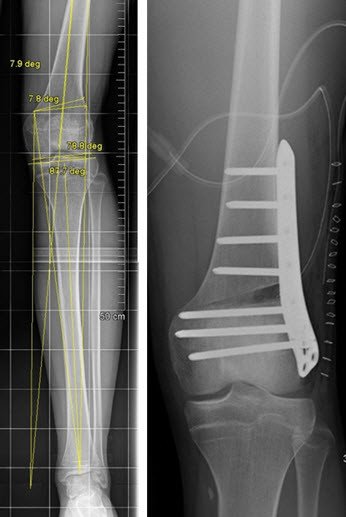

Korrektur einer Fehlstellung am Kniegelenk mit winkelstabiler Platte

Es besteht eine sehr ungünstige posttraumatische Valgusfehlstellung am Kniegelenk auf der linken Seite. Bei Belassen dieser Fehlstellung droht ein frühzeitiger Verschleiss des Gelenks aussenseitig.

Nach genauer Analyse der Deformität und Planung der Osteotomie wird eine «Opening Wedge» Osteotomie am Oberschenkel durchgeführt. Das OP-Ergebnis wird mit einem winkelstabilen Implantat gehalten.

Das klinische Ergebnis zeigt korrekte Achsenverhältnisse. Das Bein ist deutlich besser belastbar und das Risiko eines frühzeitigen Gelenkverschleisses ist minimiert.